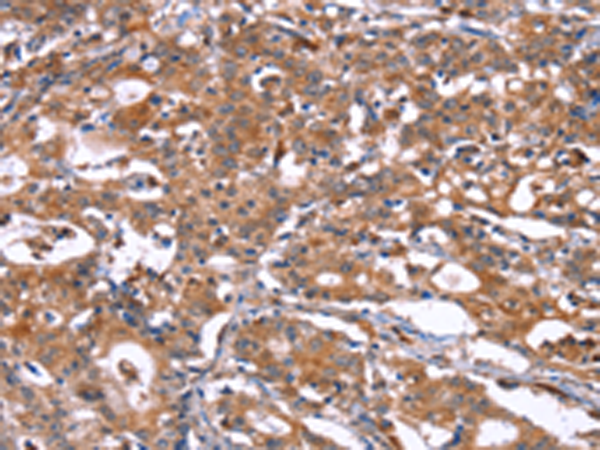

分类: 科研抗体货号: P11858别名: RANBP8应用: IHC反应种属: Human, Mouse